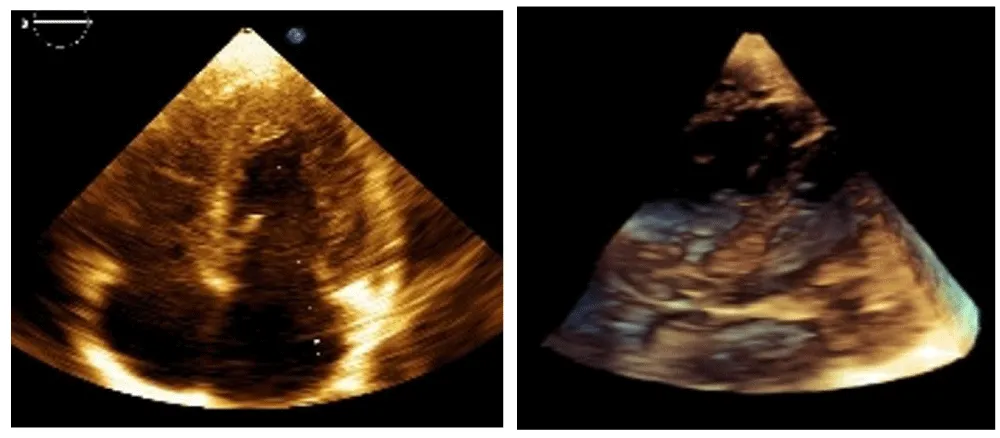

The neonatal period was complicated by infection and respiratory failure. Diagnosis occurred at 1 month due to a detected heart murmur. Echocardiography revealed cardiac rhabdomyomatosis (Figure 1 prompting clinical and genetic evaluation. A TSC2 gene (chromosome 16p13.3) mutation was identified – “c.976-15G>A”, and imaging (Gd-enhanced MRI and transcranial ultrasound) confirmed multiple SEGAs and CRs. Despite the multiple SEGA’s, no seizures have been observed in this patient.

The initial findings of cardiac rhabdomyomatosis consisted of multiple tumor-like lesions in the septum, the right ventricle, and the apex of the left ventricle, with sizes between 20 and 25 mm for the largest ones (three in number).

The best cardiac response (BCR) occurred between 4 and 6 months of therapy, with complete resolution of intracardiac tumors on echocardiography (Figure 2) [3].